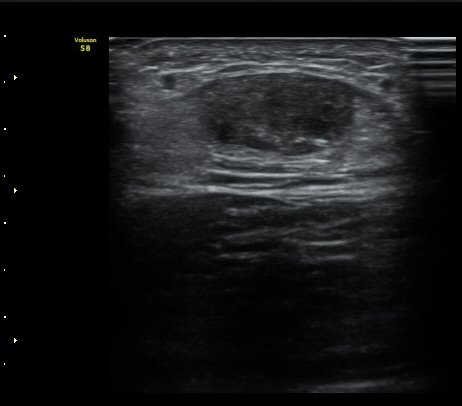

ÃÊÀ½ÆÄ °Ë»ç